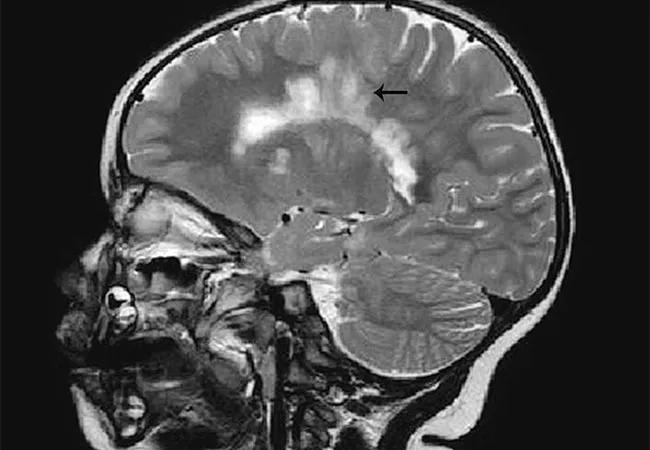

Such research opportunities are acutely needed, as pediatric MS carries a generally poorer prognosis than adult forms of the disease, warranting more investigation to improve diagnosis, treatment and outcomes. While clinical onset of MS typically occurs between ages 20 and 40, it is recognized with increasing frequency in children and adolescents. Recently improved awareness of and subspecialty training in pediatric MS have increased diagnostic accuracy and access to appropriate care.

“We have evidence that children with MS tolerate and may benefit from disease-modifying therapies,” Dr. Moodley observes, “so it’s important to diagnose pediatric MS early and accurately.” He notes that this can reduce patients’ risk of developing major motor disability and cognitive impairment early in life, as detailed in his recent Consult QD article, “MS in the Very Young.”

“Pediatric MS appears to have a narrower window of onset, with more rapid and pervasive cognitive symptoms” relative to adult MS, Dr. Rensel adds. “Pediatric MS patients experience more relapses compared with adults and have cumulative disability at a younger age. We need to improve our understanding of the underlying causes and characteristics of the disease in children and teens so we can develop better treatments.”